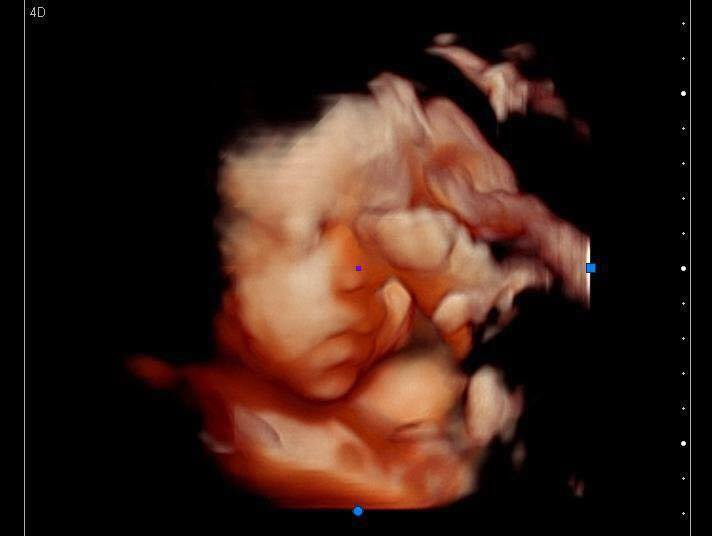

3d Ultrasound Edmond Ok

Home Anticipation Ultrasound Studio